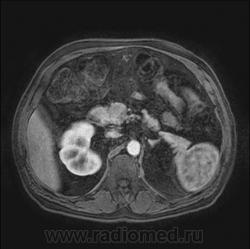

Кистозно-солидное образование н/3 правой почки, солидный компонент хоть и минимальный, но он есть, следует с ним внимательнее разобраться, я бы отнес данное кистозное образование к IV категории по Босняку.

А. эта опухоль больше похожа на "добро" или "зло"?

Добрый вечер. Босняк 4 означает что образование надо рассматривать как злокачественное, пока не будет доказано обратное или подтверждена злокачественная природа.

Сто процентный рак. Без всяких босняков.

Я бы в диф ряде рассмотрел бы эхинококкоз - в нижнем полюсе образования есть перегородка.

А вот метастазов рака почки, по видимому, не видит никто) а они есть)

Пока нет данных морфологии по этой кисте - не отказываюсь от своего мнения об эхинококке. Статьи по изолированому эхинококку почек(всего 3 процента по статистике) и других редких локализаций можно посмотреть здесь http://ifolder.ru/21262829, если кому-то еще интересна дискуссия